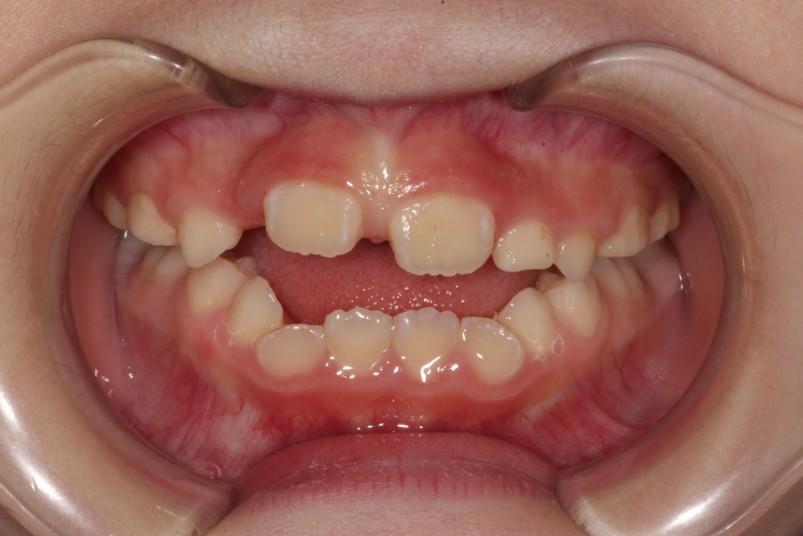

「叢生」は、一般的に「乱ぐい歯(らんぐいば)」「八重歯(やえば)」「ガタガタの歯並び」などと呼ばれる状態で、日本人に非常によく見られる不正咬合(ふせいこうごう:良くない噛み合わせ)です。

<叢生の状態>

顎(あご)の骨の大きさに対して、歯のサイズが大きすぎたり、歯が並ぶスペースが不足していたりするために、歯がデコボコに重なり合って生えている状態を指します。